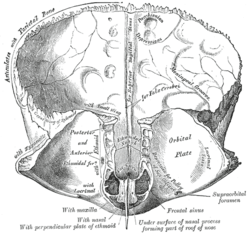

Frontal bone. Inner surface.

Frontal bone. Inner surface. Medial wall of left orbit.